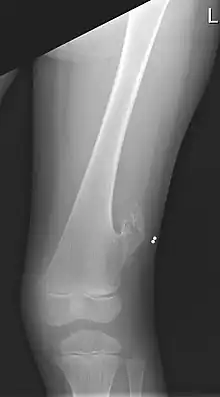

X-ray of the left femur of a 5-year-old boy with an exostosis at the lateral side, just above the knee.

An exostosis, also known as a bone spur, is the formation of new bone on the surface of a bone.[1] Exostoses can cause chronic pain ranging from mild to debilitatingly severe, depending on the shape, size, and location of the lesion. It is most commonly found in places like the ribs, where small bone growths form, but sometimes larger growths can grow on places like the ankles, knees, shoulders, elbows and hips. Very rarely are they on the skull.